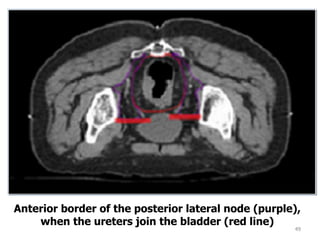

Anterior border of the posterior lateral node (purple),

when the ureters join the bladder (red line)

49 Anterior border ofthe posterior lateral node (purple), when the ureters join the bladder (red line)